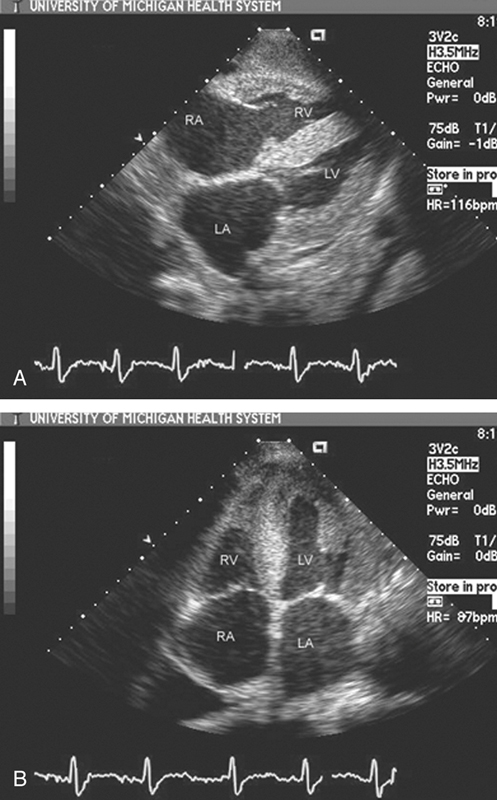

فحوصات تشخيصية لبعض امراض القلب والشرايين التاجية